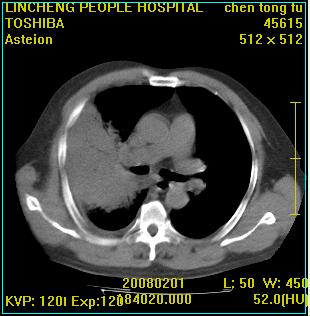

患者,男性,62岁。主因头晕,发热,咳嗽6天,高热达39度,esr19mm/h,wbc 3.9×10 9/l

大叶性肺炎并胸膜炎

右肺大叶性肺炎,胸腔积液。建议痰检。

实变区见空气支气管征,支气管通畅,考虑为大叶性肺炎,右侧少量胸水

1)考虑为:右肺感染性病变。建议:抗炎治疗复查。2)右侧少量胸腔积液。

考虑为右肺大叶性肺炎,胸腔积液,建议必要时纤维支气管镜检查,以排除肿瘤性病变。

右肺炎症并右侧胸腔少量积液。

考虑为右肺大叶性肺炎伴少量胸腔积液,建议复查,如病变不吸收或吸收不明显,建议纤维支气管镜检查,除外细支气管肺泡癌的可能。

右侧大叶性肺炎,右侧少量胸腔积液.